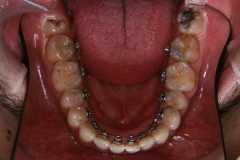

上下奥歯も含めた透明ブラケット矯正による治療例

上下すべての歯に透明なブラケットをつけて全体的な治療を行っています。